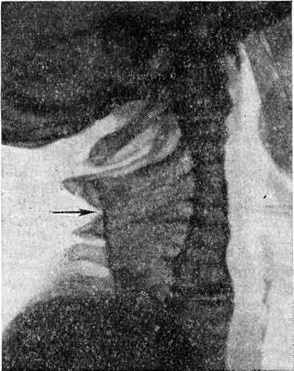

Рис. 1.

Томограмма шеи в боковой проекции при болезни Клиппеля—Фейля: характерная деформация (слияние позвонков) шейного отдела позвоночника (указано стрелкой).

Диагностика заболевания основывается на клинические, симптомах с обязательным рентгенологическое обследованием шейного и верхнегрудного отделов позвоночника в задней и боковой проекциях. При очень короткой шее на рентгеновское изображение шейного отдела позвоночника в прямой задней проекции накладываются тени костей лицевого черепа и затылочной кости. В подобных случаях рентгенограмма, а тем более томограмма в боковой проекции (рисунок 1), как правило, выявляют все характерные детали и позволяют с уверенностью поставить правильный диагноз.